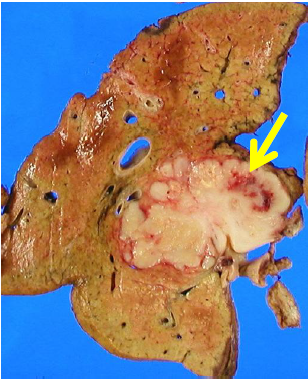

診断では造影CTまたはMRI検査の動脈相および平衡(静脈)相であまり濃染しないことが特徴です(図3)。

図3 肝内胆管癌のCT: 動脈相で濃染せず低吸収を呈する腫瘍(矢印)